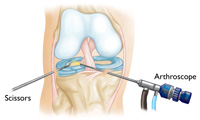

If your symptoms persist with non-surgical treatment, Dr. Ahmad may suggest arthroscopic surgery.

- Knee arthroscopy: One of the most commonly performed surgical procedures, includes inserting a miniature camera into the knee through a small incision. This provides a clear view of the inside of the knee, which Dr. Ahmad uses to insert surgical instruments through to trim or repair your tear.